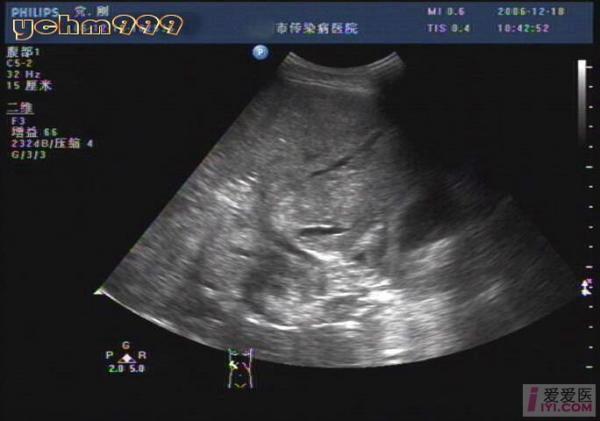

酒精性肝硬化伴肝ca,门脉血栓

肝脏超声诊断

不像脂肪肝,像酒精性肝病